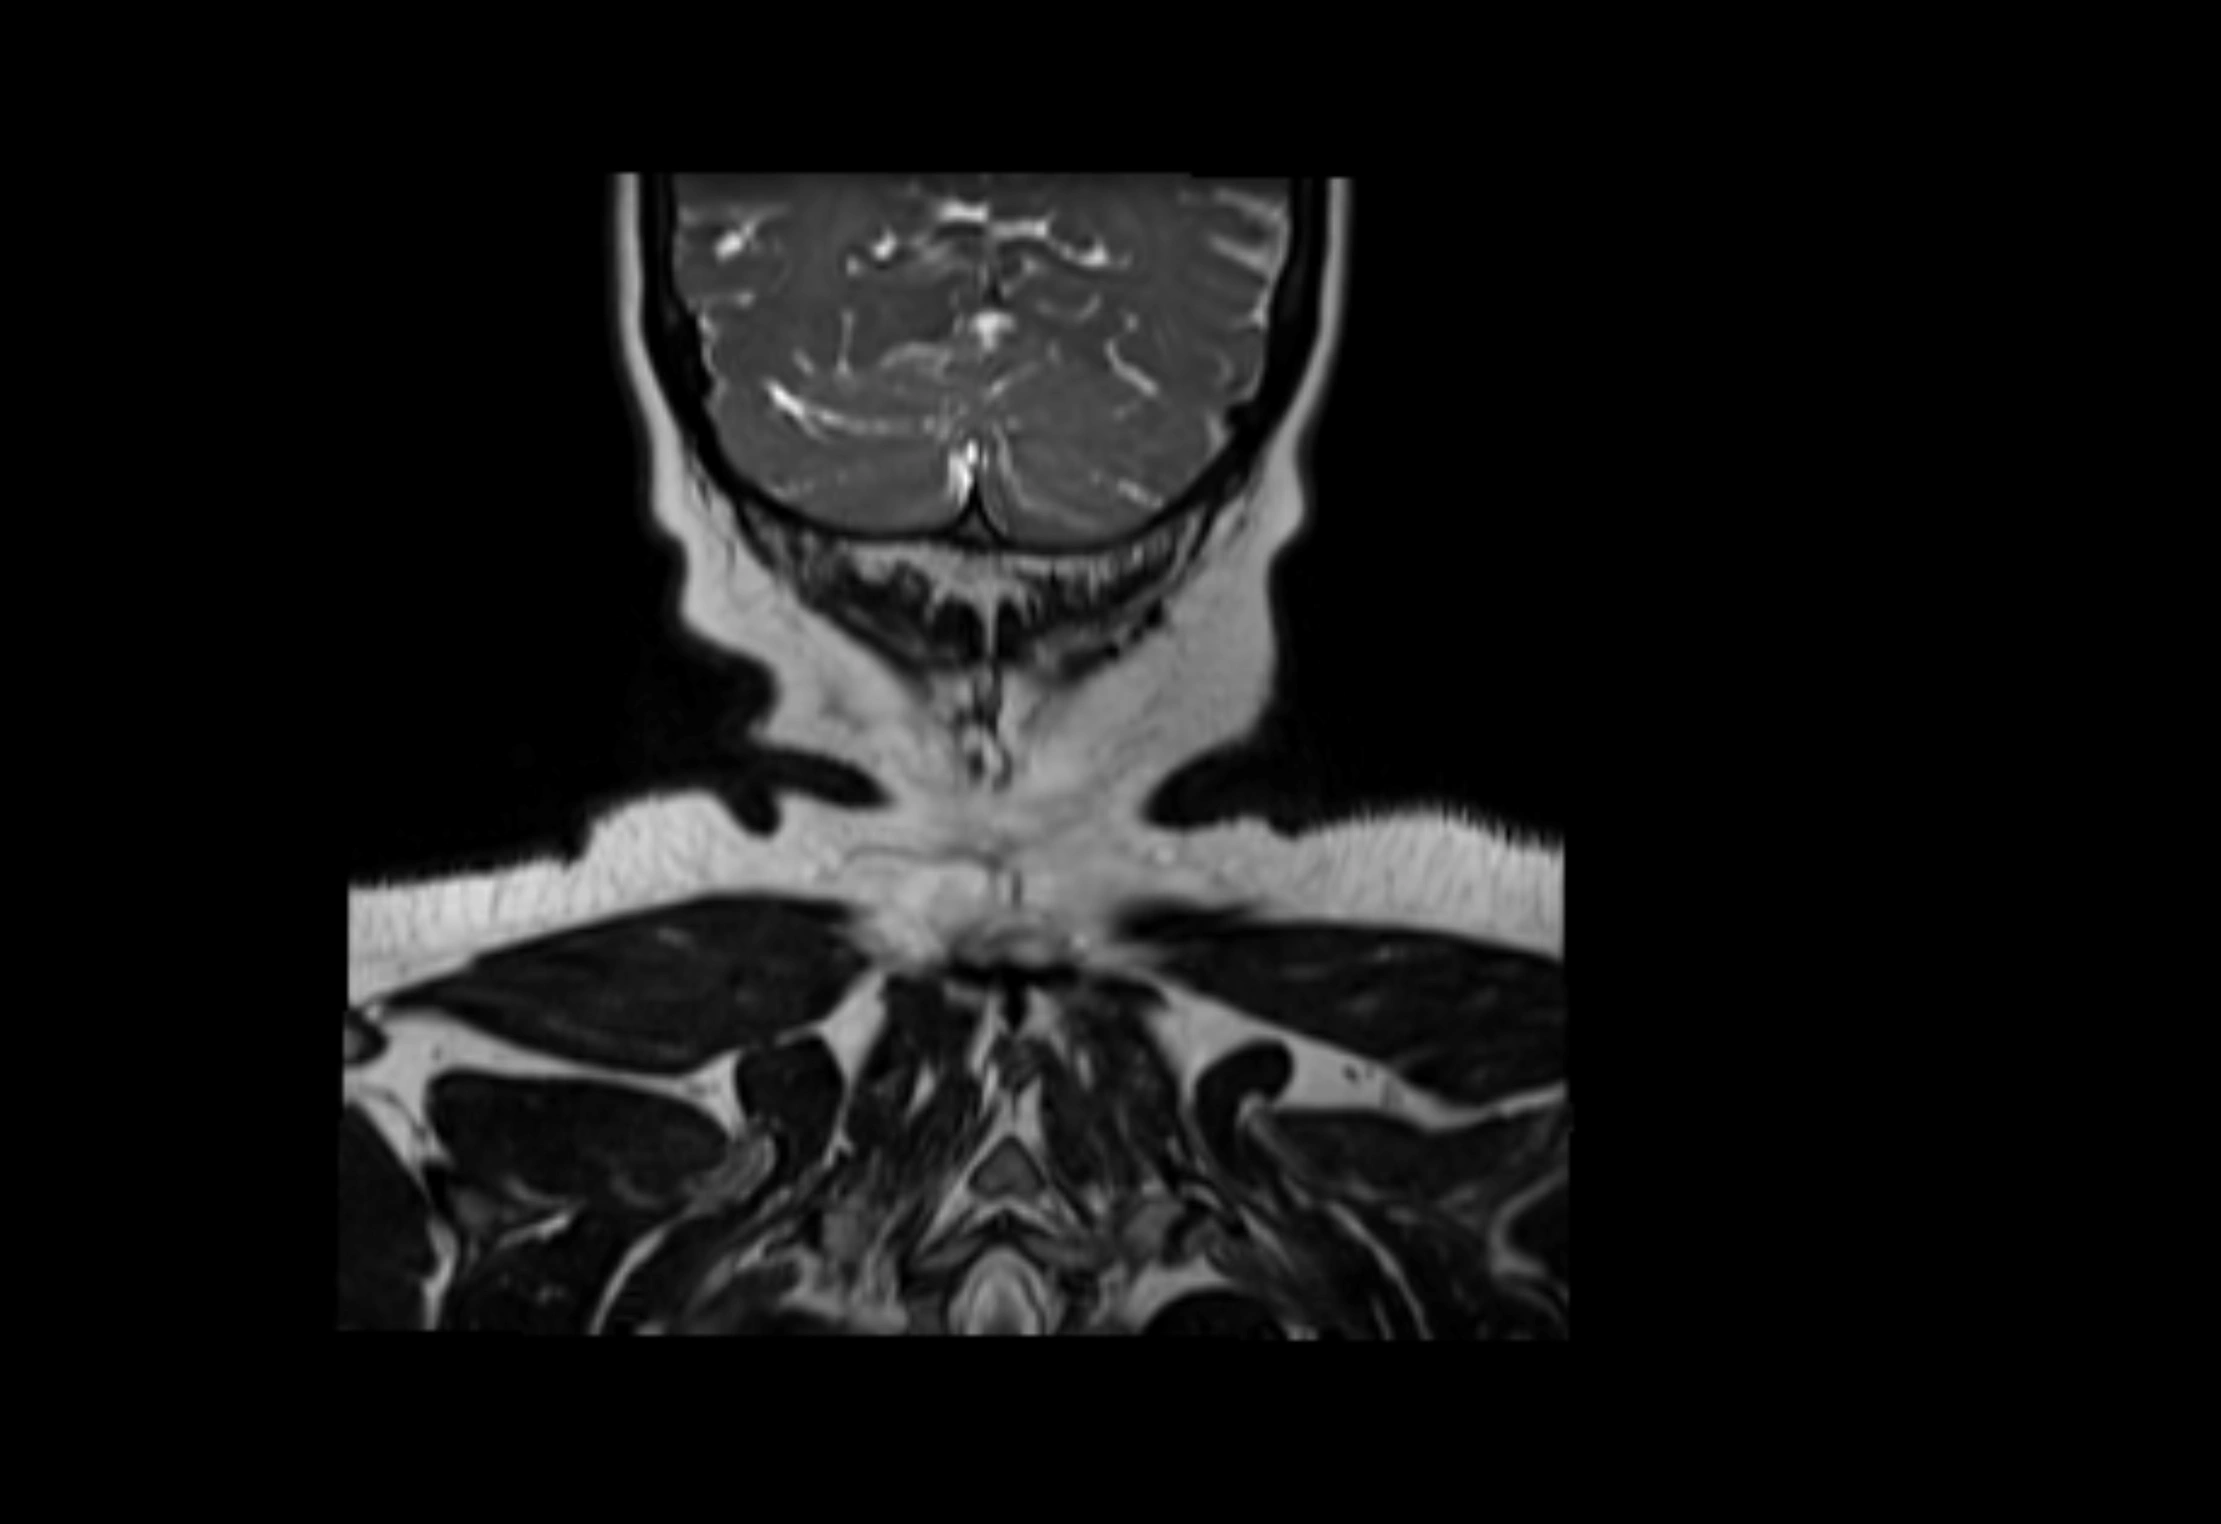

MRI Appearance

T2-weighted images:

• Nodes show intermediate signal, with surrounding fat bright

• Useful for detecting edema, inflammation, or infiltration